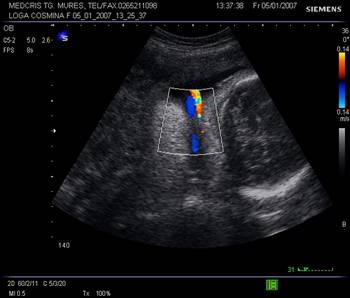

Arterele spiralate si placentomul. Dupa 28 sapt. mici ecouri anecogene rotunde apar in substanta placentara, reprezentand centrul placentomului - mica unitate de flux, unde se deschid artere spiralate. Cu ajutorul Doppler-ului color se poate urmari ejectia sangelui din arterele spiralate.

Vascularizatia uterina crescuta in trim. III, in peretele uterin nu trebuie confundata cu un hematom retroplacentar.

Fig nr.213 Vascularizatie a peretelui uterin subplacentara, ce nu trebuie confundata cu hematomul retroplacentar

Fig. nr.222. Hematom

la nivelul placii deciduale a

placentatiei la 10 sapt. , cu intreruperea vascularizatiei la Doppler color (

sageata ). Se remarca vascularizatia cordonului ombilical si insertia centrala

a acestuia in placenta